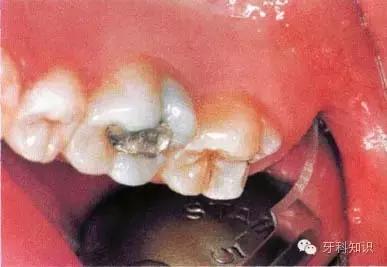

女性患者,40岁。第Ⅰ类,A分类。右下颌第三磨牙阻生,口内可见部分牙冠。黏骨膜瓣切口设计为:远中切口由距离第二磨牙15 mm或更多处开始向前切开,颊侧切口不超过第二磨牙

使用手机上的圆钻显露牙冠最大周径,远中方向显露至釉牙骨质界,颊侧显露至近中颈部

用缝线穿过舌侧软组织并将其拉向舌侧,以避免其受损并保证术区视野清晰。切割牙冠前先将牙根挺松。图示为用合适的牙挺楔入挺松的牙根下面